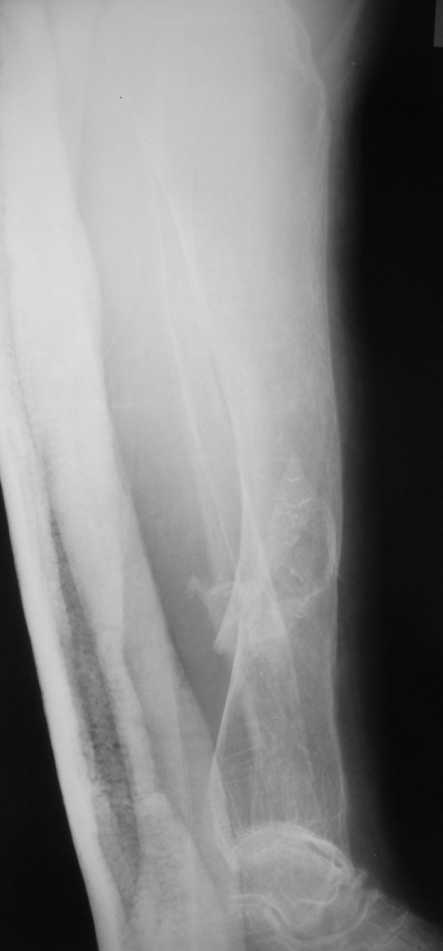

Но даже при малоинвазивной методике лечения применимой для даной больной существуют следующие проблемы: выраженный остеопороз, тонкий кортикал, очень широкий канал.

Контрольные рентгенограммы прилагаю.

Проблема в том, что в сагитальной плоскости угол голеней =30 градусам. Ширина канала 30.

Если при введении стержня будет видно, что из-за искривления дело идет к перфорации стенки, надо будет сделать чрескожную остеотомию на уровне кончика стержня.

ДС> Будет ли остеосинтез стержнем стабильный?

Во-1-х, интрамедулярный остеосинтез относится к методам, дающим относительную, не абсолютную стабильность. Во-2-х, стабильность неплохо обеспечивается запирающими винтами. В-3-х, несоответствие кривизны стержня и канала приводит к повышению стабильности, в-4-х, канал можно искусственно сузить введением отклоняющих (трансмедуллярных, Poller) винтов.

ДС> И возможны ли другие варианты остеосинтеза?

Конечно, возможны - любые существующие. Но оптимальным из возможных здесь однозначно является закрытый интрамедуллярный остеосинтез.